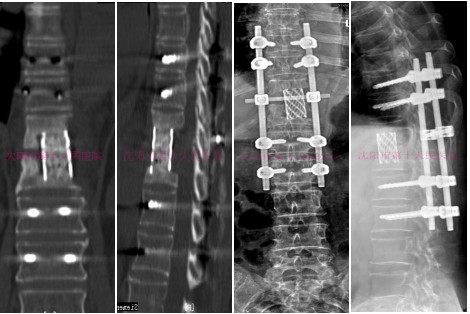

术后DR提示:脊柱侧凸畸形矫正,脊柱序列整齐。

术后CT显示:椎体病变处清除彻底,椎间钛网植骨融合位置满意,植骨充分,加压可靠,椎弓根固定坚强。

术前DR:内固定及钛网位置满意

术后三维CT提示:脊柱恢复正常序列,椎体间病灶清除彻底,椎管内无游离碎骨块,内固定位置良好。